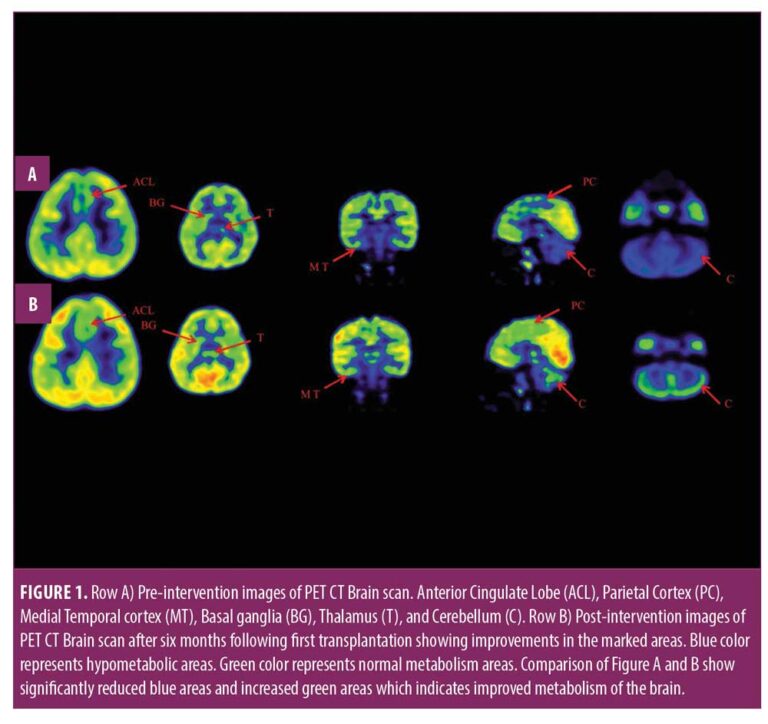

本報告中,我們治療了一名患有痙攣性雙癱性腦癱的兒童,在對康復反應有限后,采用了多種細胞療法。臨床改善的結果與客觀量表相關,例如粗大運動功能測量 (GMFM)、粗大運動功能分類系統 (GMFCS) 以及功能獨立測量 (FIM) 和 (PET CT) 腦成像研究。

在認知上,由于他定期上學,他的注意力持續時間和坐姿耐受力也得到了改善。GMFM分數從60.67提高到67。GMFCS等級由3級提升至2級;FIM評分從97分提高到99分。比較第一次細胞治療之前和之后7個月期間進行的腦部PET CT掃描結果,發現前扣帶回葉、頂葉皮層、內側顳葉皮層、丘腦、基底神經節和小腦(表1)。

在此,我們通過客觀量表(如FIM、GMFM和GMFCS)和正電子發射計算機斷層掃描腦神經影像對比研究來監測細胞療法后的療效。在16個月的治療過程中,GMFM評分從60.67分提高到81.88分,其中坐的領域從59分提高到60分,爬行和跪的領域從32分提高到40分,站的領域從6分提高到27分,走、跑和跳的領域從8分提高到32分。GMFCS 分級從第3級提高到第2級,因為孩子能夠騰出雙手坐在椅子上,能夠在沒有幫助的情況下在平整的地面上行走和奔跑,還能夠扶著欄桿爬樓梯。FIM分數從91分提高到99分,這表明他的功能狀況有所改善。

這項研究表明,多種干細胞療法結合神經康復可有效改善腦癱患者的粗大運動功能和功能獨立性。自體BMMNC多次移植后進行強烈的神經康復可加快神經再生過程,這反過來又反映了患者殘疾程度和生活質量的積極結果。PET CT掃描可以有效地用于監測干預后細胞水平發生的變化。因此,多細胞療法是安全、可行的,并且可以有效地與腦癱的神經康復相結合作為增強治療。